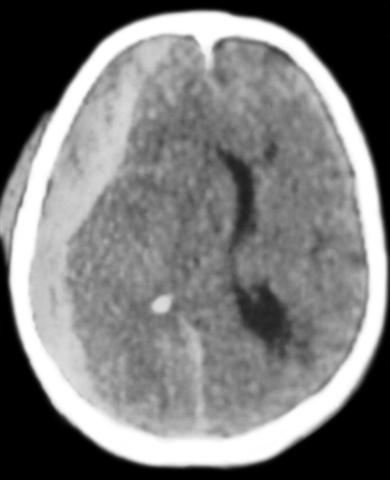

Рис. 1. Компьютерная томограмма головы при субдуральной гематоме после черепно-мозговой травмы.